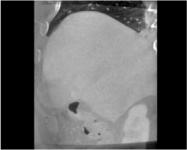

An example of CT/CBCT and MR/CBCT registration results are shown in figures 3 and 4, respectively. For both cases, the CBCT image (first column) was acquired intra-operatively after needle insertions and was employed as a reference for image registration. The pre-operative image is displayed before registration (second column), after PM-EA (third column) and after PM-EA+Evo (fourth column). The occurrence of patch shifts is reported for each spatial direction in panels (m–o): for each histogram, the shift with maximal occurrence is shown by the red dashed line. For panels (a–l), a ROI — manually defined on the CBCT image/encompassing the liver — is shown using red dash lines. Our visualization shows an improved correspondence of the contour of the liver with the manually defined liver boundary when the PM-EA solution is employed (see 3(c,g,k) and 4(c,g,k)). Moreover, an even better correspondence of the contour is observable using the PM-EA+Evo solution (see 3(d,h,l) and 4(d,h,l)).

Trans.

[X-Y]

CBCT

(a)

CT / No registration

(b)

CT / PM-EA

(c)

CT / PM-EA+Evo

(d)

Sag.

[X-Z]

(e)

(f)

(g)

(h)

Cor.

[Y-Z]

(i)

(j)

(k)

(l)

(m)

(n)

(o)